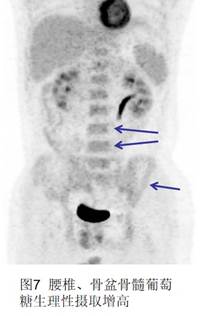

7、骨髓。通常骨髓的FDG攝取程度比較低,但經(jīng)歷了粒細胞刺激因素的治療后的患者(如化療后)會出現(xiàn)骨髓彌漫增高(圖7)的FDG攝取。